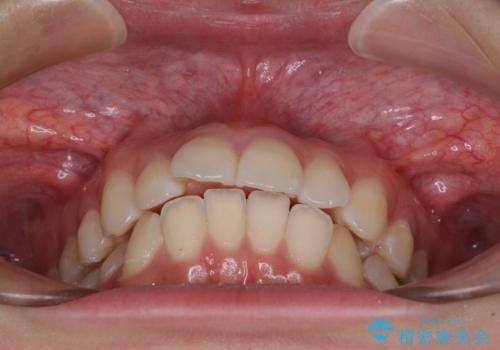

- 飛び出した上の前歯やデコボコを気にして来院された患者様です。

上下前歯の突出感とデコボコを気にして来院された患者様です。

インビザラインによる上下歯列の側方拡大と後方移動、必要に応じてIPR(歯と歯の間を削る)によりスペースの獲得により歯列を整えることとしました。

治療途中、出産や転居があり、2年ほど治療期間が長くなってしまいましたが、前歯の歯並びや飛び出した感覚を無事に改善させることができました。